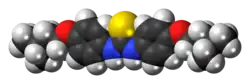

| 3D model (JSmol) | |